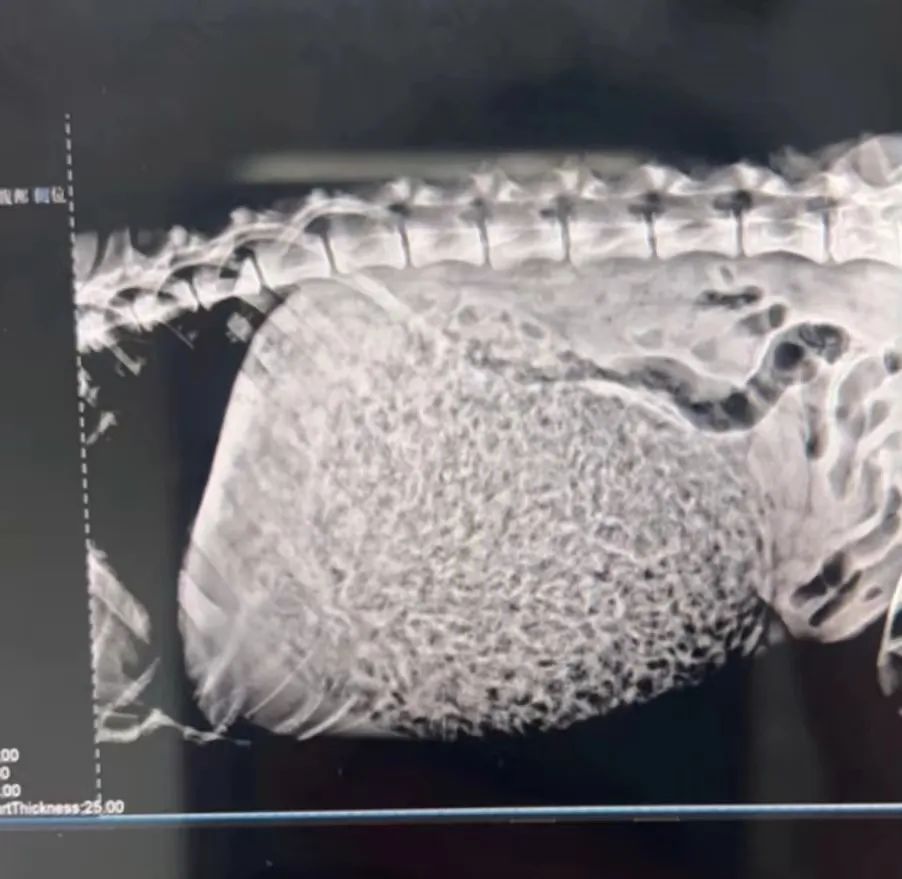

送到医院一顿操作,

医生看着这满满当当的片子,

只能初步判断是一条毛巾。

结果,医生开刀后才看清:

居然是满满一肚子的狗粮!!!!

而取出的狗粮一称足有8斤多!

加上垫肚子的那1~2斤,

也就是说大壮足足炫了10斤狗粮!

看这狗粮的干燥和完整程度

狗哥推断大壮是直接吞的